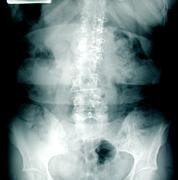

Radiographic weightbearing imaging studies were performed to evaluate the patient's lumbar spine and hips. There was marked reduction in disc height, retrospondylolisthesis of the first lumbar vertebra onto the second lumbar vertebra with reduction in size of foramen. There were proliferative osteophytes (overgrowth of bone forming hard bars) and moderate anterior traction spurring demonstrated. There was right laterolisthesis of the spinous processes accompanied by right concavity scoliosis. The acetabuli and hip joint spaces were well-maintained.

The ways that a foramen may be diminished in size are basically threefold: loss in disc height, subluxation of facets, and stenosis, or narrowing of the intervertebral foramen. In the presence of instability, the lax facet capsule allows the superior facet to move backward and forward with rotation. In this patient, the spinous process of L1 and L2 have been rotated; the superior facet moved anteriorly; the joint space had opened and the lateral canal was markedly narrowed. In the presence of fixations or advanced degenerative changes to stabilize the affected segment, little or no movement should take place at affected level. The lateral canal is fixed because of the degenerative deformity. Thus, two factors may be involved in producing the entrapment: subluxation of posterior facets, (superior facet moves superior and anterior), and enlargement of facet by osteophytic involvement that further narrows the lateral canal. The diagnostic imaging of choice is a CT scan.